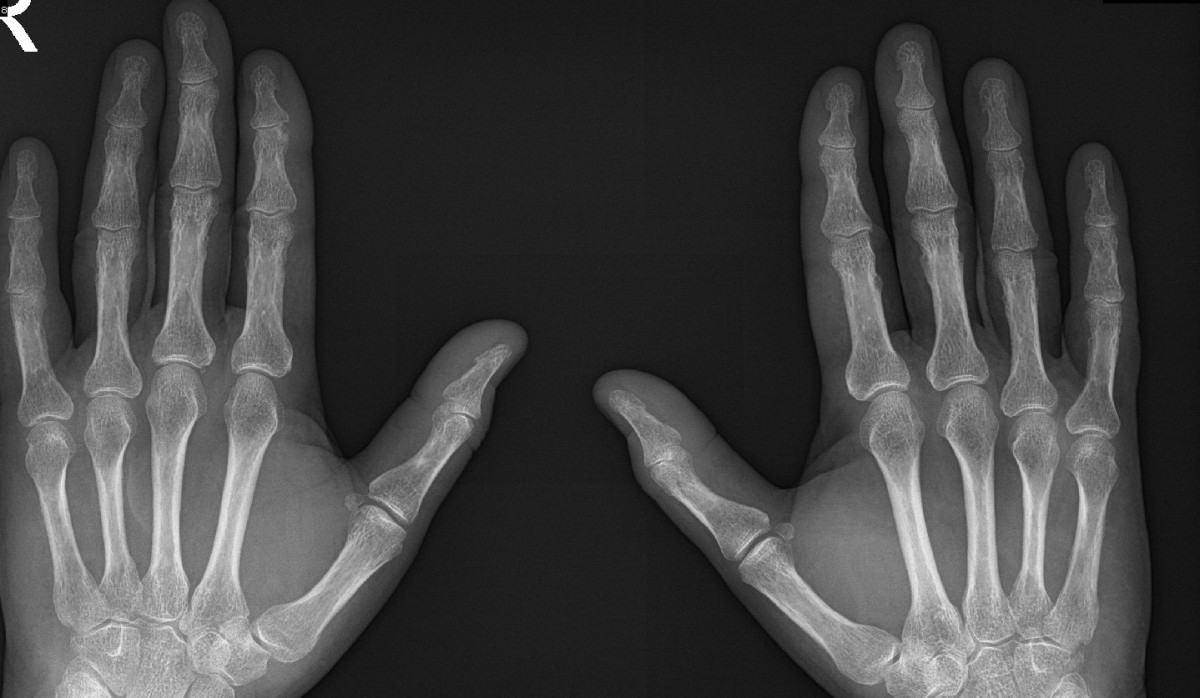

Vážené odborné kolegium. Obracím se na Vás se žádostí o radu s diferenciální diagnostikou pacienta s akrální osteolýzou distálních článků 1.-3. prstu pravé a 1.-2. prstu levé ruky, které se vyvinuly během necelých dvou let. Pacient je 67letý muž, nekuřák, profesí učitel, hraje na kytaru, v rodině bez přítomnosti revmatologických či autoimunitních onemocnění. V anamnéze nemá příznaky Raynaudova syndromu, lupénku, úraz rukou, vystavování rukou nadměrné zátěži či chladu ani expozici polyvinylchloridu. Také nemá v rodině žádné vrozené onemocnění postihující kosti či lupénku. V 4/2022 byla u něj provedena operace syndromu karpálního tunelu vlevo, v 6/2022 byla provedena operace syndromu karpálního tunelu vpravo. Od operace u něho dochází postupně k bolestivému omezení pohyblivosti prstů na obou rukou a asi rok od operace (od léta 2023) se vyvíjí zkrácení a rozšíření distálních článků 1. -3. prstu vpravo a 1.-2. prstu vlevo, na stejných prstech dochází ke ztrátě průhlednosti nehtů (nehty jsou mléčně zabarvené, ale hladké). Pro problémy se šlachami byla 11.1.2024 provedena operace flexorových šlach prstů pravé ruky (1.-5. prst) ve Vysoké n. Jizerou zatím bez většího efektu.

Můj dotaz směřuje k překvapivému nálezu na rtg z 26.1.2024, kde je patrna osteolýza centrálních částí distálních článků I-III. prstu pravé ruky a 1.-2. prstu levé ruky, dle rtg terminologie midshaft resorption (band acro-osteolysis). Přitom na rtg v 3/2022 tento nález nebyl přítomen. Viz příloha. U pacienta není zvýšené CRP, kostní ALP, hodnoty Ca a parathormonu jsou v normě, není přítomen RF, anti CCP, anti ds-DNA, anti-Scl ani ani-centromery. RTG plic, RTG SI kloubů a rtg kloubů nohou je s normálním nálezem. Objektivní nález tento týden: normální, výška 173 cm, hmotnost 79 kg, BMI 26,4 kg/m2, kloubní nález: omezeno dovření prstů obou rukou, mírně omezena dorzální flexe v obou zápěstích, rozšíření distálních článků 1.-3. prstu na pravé ruce a 1.-2. prstu levé ruky, bílé zabarvení nehtů na uvedených prstech, prsty prokrvené, bez trofických změn, palpační bolestivost DIP 2-3 bil., PIP 2-3 bil., lehký difusní otok na dorzu pravé ruky (udává od operace šlach) a 2.-3. prstu bil. Palpačně bez známek synovitidy, na UZV provedeném revmatologem sporné malé množství tekutiny na dorzu pravého zápěstí a zesílení šlach zejména 2. a 3. prstu bil. (bez lemu tekutiny), doppler neg. V literatuře je udáváno několik příčin akroosteolýzy: idiopatická, po expozici polyvinyl chloridem, po vystavení chladu, traumatu, u autoimunních onemocnění (systémová sklerodermie, psoriatická artritida), u infekce (lepra), u endokrinologických onemocnění (hyperparathyreosa, diabetes mellitus), vrozené (Hajdu-Cheney syndrom a Gaucherova choroba)

Dle popisu rentgenoložky vyjímám: "na RTG rukou z března 2022 je přítomna zúžená štěrbina většiny DIP, eroze DIP 2 dx, sporná na MCP 3 dx., kde je drobná kalcifikace. Na RTG rukou z letošního ledna již eroze nejsou přítomny, na DIP 2 se možná sumuje, na MCP je stále kalcifikace. Dále samozřejmě destrukce diafýz dist. článků. Vzhledem k návaznosti na nehtová lůžka by se asi mohlo jednat o psoriatickou artritis, i když to není morfologicky moc typické, obdobný obrázek může být u hyperparathyreosy, zejm. sek. - např. u renální osteodystrofie, k tomu by dokázala najít i další změny jako tubulizace kortikalis nebo výše uved. kalcifikace při MCP. Tato by podpořila i sklerodermii, která by myslím mohla odpovídat i jeho problémům s flexí prstů. "Pacient byl léčen kortikoidy v malé dávce (spíše na vlastní žádost) a to od 4/2023 až do 1/2024, efekt byl, ale ne úplný, léky vysadil před plánovanou operací šlach v 1/2024, po vysazení se zdá opět zhoršení pohyblivosti prstů, proto byly tento týden navráceny.

Akro-osteolýzu občas vidíme, hlavně u pacientů se sklerodermií. Ale to je většinou terminálně uložené. Tento typ midshaft (band) lysis jsem nikdy neviděl. Hledal jsem podobné případy v literatuře. Našel jsem dva případy u kytaristů. Jeden z nich je velice podobný svým vzhledem lýzy uložené pásovitě uprostřed distálních článků. Druhý případ je méně podobný. U obou jsou ale lýzy přítomné jen na levé ruce.

Našel jsem ale také jeden podobný obraz band-osteolysis na Radiopedii (radiopaedia.org/articles/acro-osteolysis-1 ), který je připisován hyperparathyreoze, a další v jiné publikaci (Colquhoun M, Penn H. Band acro-osteolysis in systemic sclerosis. Rheumatology (Oxford). 2021 Oct 2;60(10):4945. doi: 10.1093/rheumatology/keab031. PMID: 33493313, pubmed.ncbi.nlm.nih.gov/33493313/), který je u sklerodermie. U obou těchto diagnóz, pokud jsou publikovány obrázky akro-osteolýzy, tak jsou ale většinou terminálně, tedy vypadají jinak.

V tomto případě, při absenci jakýchkoli dalších abnormalit, bych myslel asi na možnou souvislost s traumatizací strunným nástrojem. Snad při senzibilizaci po operaci KT (?). Konkrétně jsem ale zmínku o takovém vztahu nikde ani náznakem nenašel.